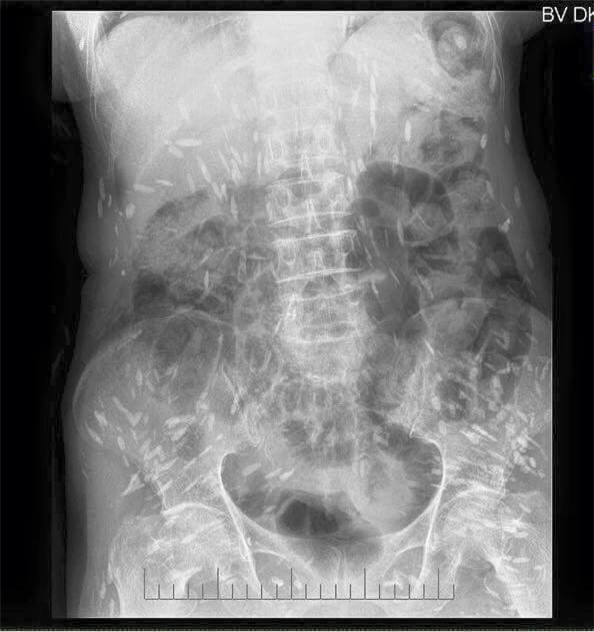

Mấy ngày nay trên mạng chia sẻ hình ảnh phim chụp Xquang của một bệnh nhân bị sán dải lợn, ấu trùng sán lợn di chuyển khắp cơ thể.

Hình ảnh đang lan truyền trên mạng xã hội được cho là của bệnh nhân đã khám và điều trị tại Bệnh viện Đa khoa trung ương Thái Nguyên. Bức ảnh được rất nhiều người chia sẻ kèm theo lời cảnh báo từ nay nên nói không với các loại thịt tái, sống, rau sống, tiết canh.

Hơn 30 năm gắn bó với chuyên ngành ký sinh trùng, bác sĩ Đề cho rằng hình ảnh này rất phổ biến, may mà ấu trùng sán lợn chưa lên não.

Bác sĩ Đề cho biết có bệnh nhân ông gặp có 300 ấu trùng sán lợn ở não và 300 ấu trùng sán lợn ẩn dưới da. Các loại ấu trùng này chụp Xquang có thể nhìn được hết.

(Ảnh: fb BS Luong Quoc Chinh)

Bệnh ấu trùng sán lợn ở người do ăn phải trứng sán dây lợn dưới dạng lợn gạo. Nang ấu trùng sán lợn ở người dài hơn ở lợn, nang sán tập trung thành chùm như chùm nho, kích thước đến 10 - 20 cm chứa tới 60ml dịch.

Nang ấu trùng sán lợn ký sinh dưới màng nhện của não có kích thước tới 10 - 15cm. Một vật chủ có thể nhiễm tới hàng trăm ấu trùng